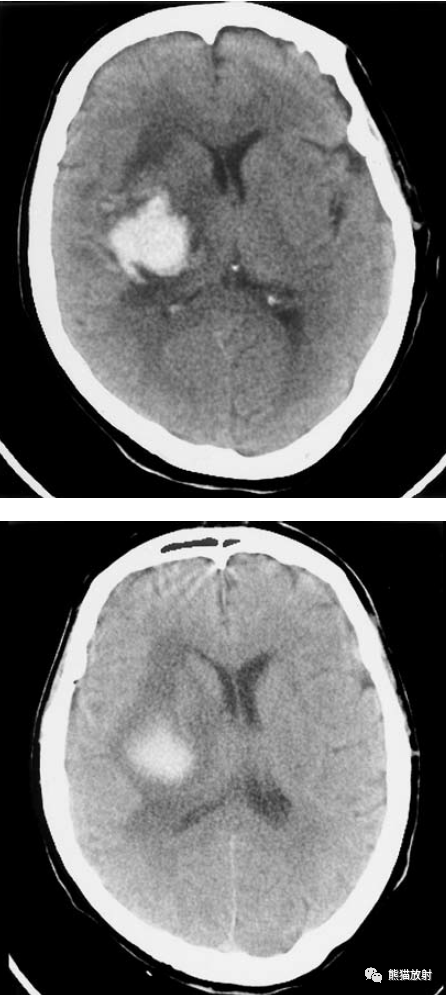

脑实质内出血的演变,分布,ct表现

脑实质内出血丨演变,分布,ct表现